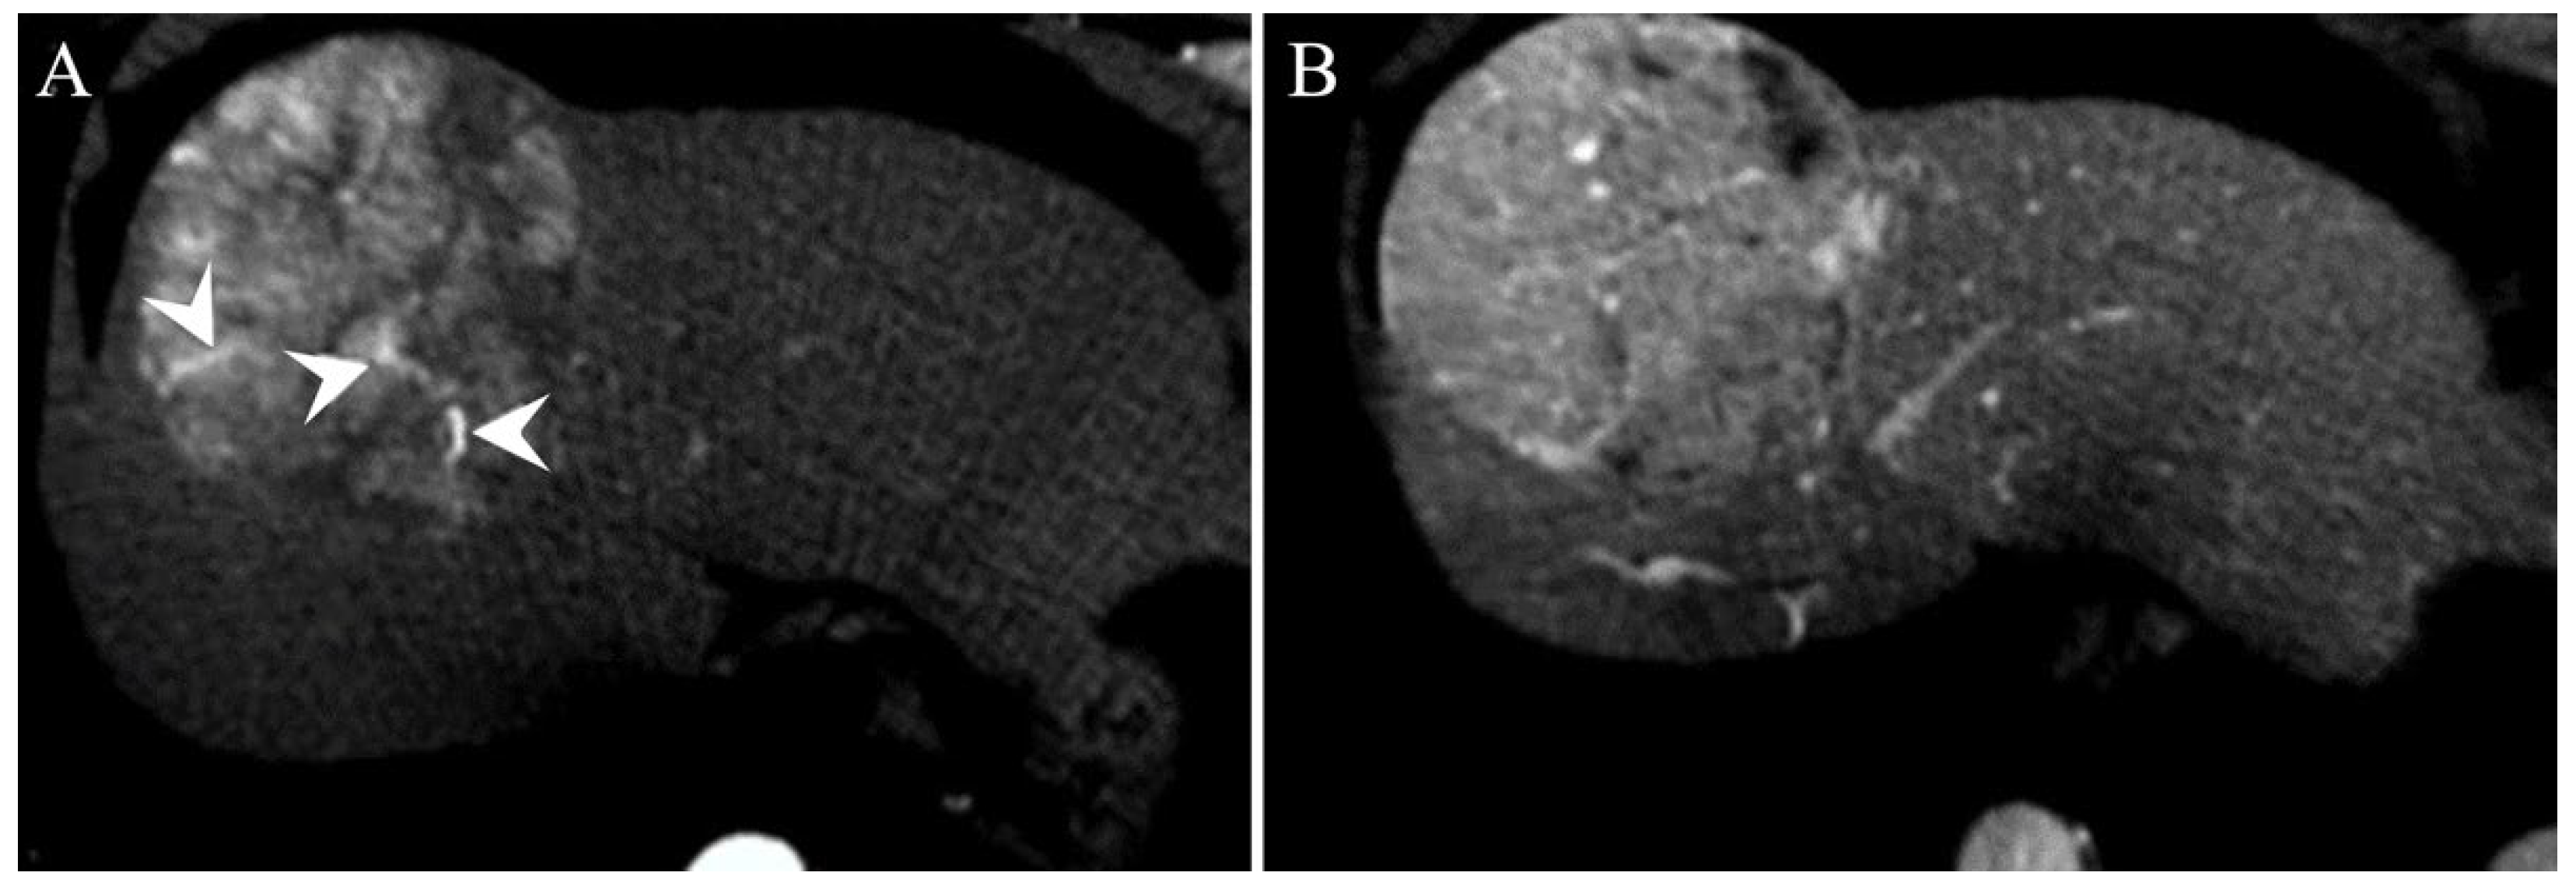

| TTPVI | 14 (38.9%) | 11 (20%) | 0.058 |

| TTPVI | 2.058 (1.103–3.124) | 0.015 | 2.349 (1.369–4.032) | 0.002 |